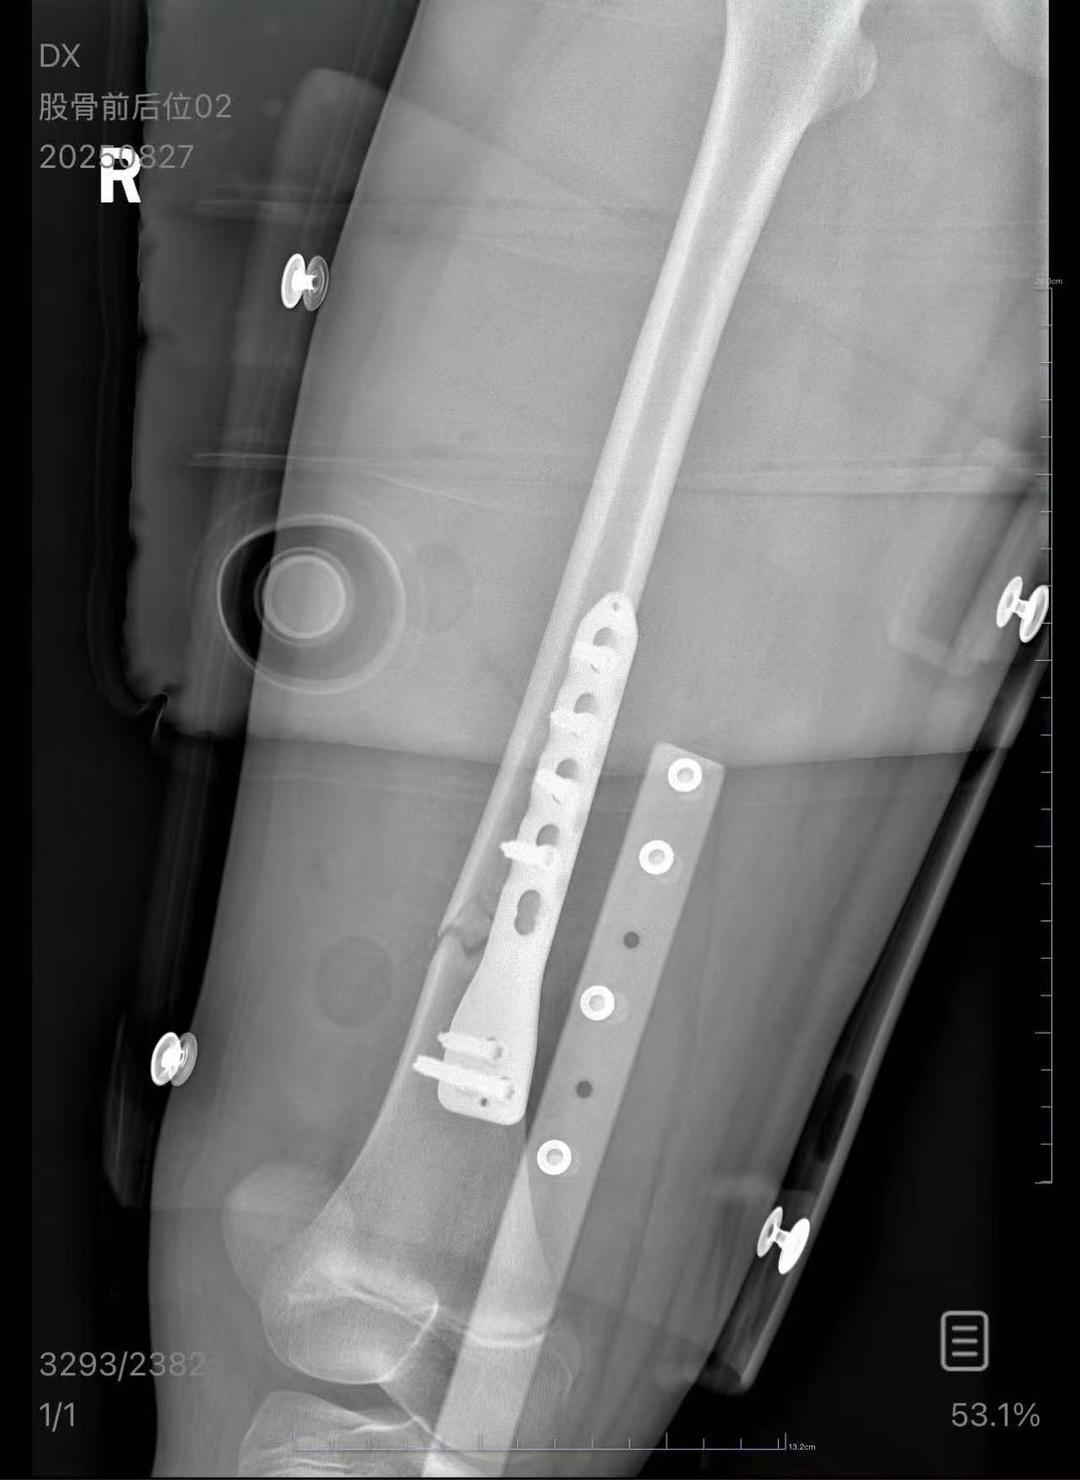

朱女士女儿手术后拍的X光片(受访者供图)

医院病历显示,8月24日凌晨,朱女士的女儿因右股骨骨折入院,需住院进一步治疗。